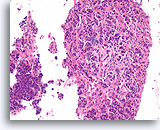

Ductaal carcinoom, Borst FNA, Celblok.

Dit plaatje toont geen normale lobulaire architectuur en de stromale fibroblasten zijn niet goed uitgelijnd met de ductale cellen (pijl). Invasiviteit kan echter niet met zekerheid worden gediagnosticeerd omdat de maligne ductale cellen in dit gebied ronde aggregaten vormen met een gladde, dichte, collagene laag die hen van het stroma scheiden. Soortgelijke patronen kunnen worden waargenomen als een ductaal carcinoom in situ zich uitbreidt tot sceloserende adenose. Een afwezigheid van myoepitheliale cellen volgens IHC kan helpen aantonen dat deze focus invasief is [12].

40x

Ductaal carcinoom, Borst FNA, Celblok.

Dit plaatje toont geen normale lobulaire architectuur en de stromale fibroblasten zijn niet goed uitgelijnd met de ductale cellen (pijl). Invasiviteit kan echter niet met zekerheid worden gediagnosticeerd omdat de maligne ductale cellen in dit gebied ronde aggregaten vormen met een gladde, dichte, collagene laag die hen van het stroma scheiden. Soortgelijke patronen kunnen worden waargenomen als een ductaal carcinoom in situ zich uitbreidt tot sceloserende adenose. Een afwezigheid van myoepitheliale cellen volgens IHC kan helpen aantonen dat deze focus invasief is [12].

40x